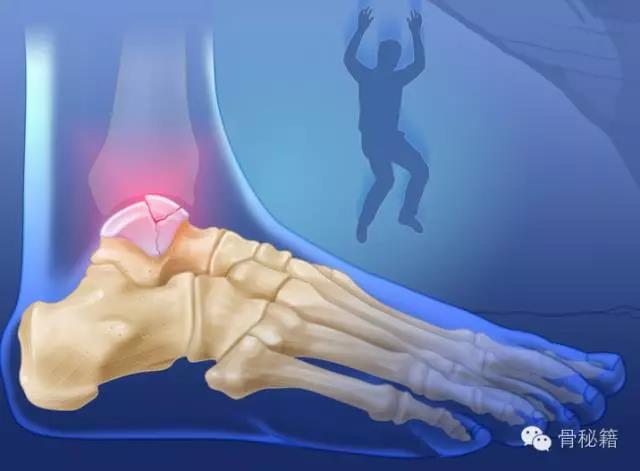

距骨----是一个很厉害的骨也是一个很烦人的骨

厉害在哪里?全身的重量都传导到它一个骨进行负重

损伤主要位于以下几个主要部分体、颈、后突、外突

当发生骨折脱位时,由于位移巨大,导致相应位移的血管损伤、最终导致距骨坏死所以距骨骨折的分型常用Hawkins分型距骨坏死率随分型严重程度逐渐增加